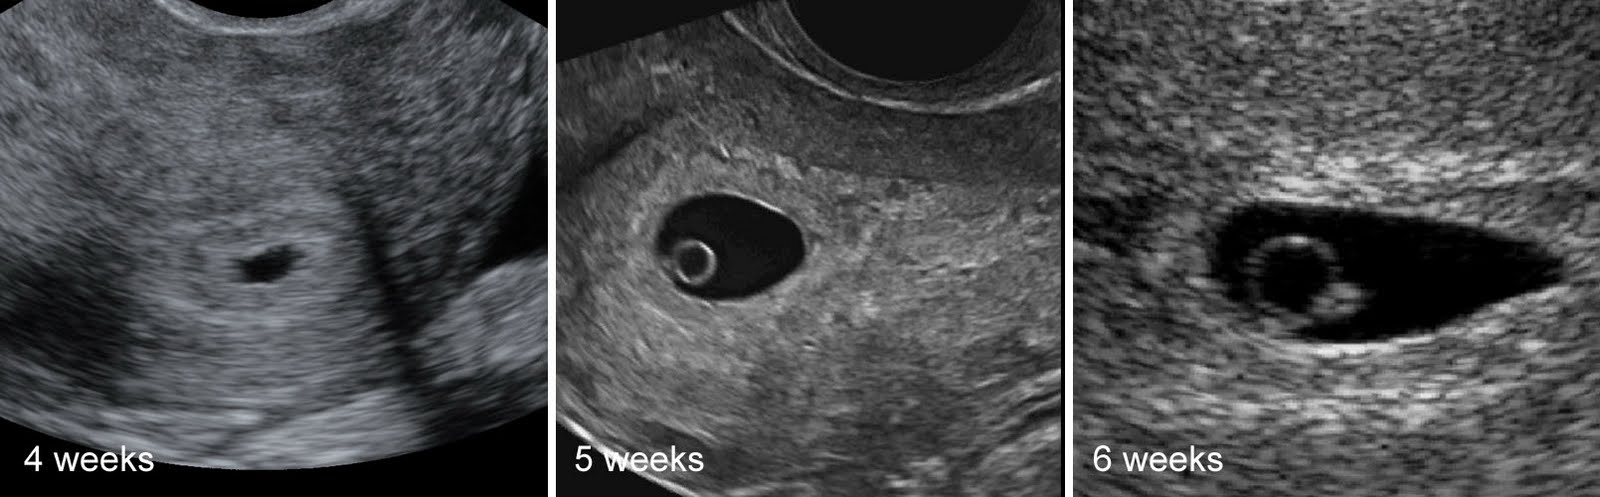

Развитие эмбриона: Что происходит на 3 неделе беременности

Раздел: Фотопанорама